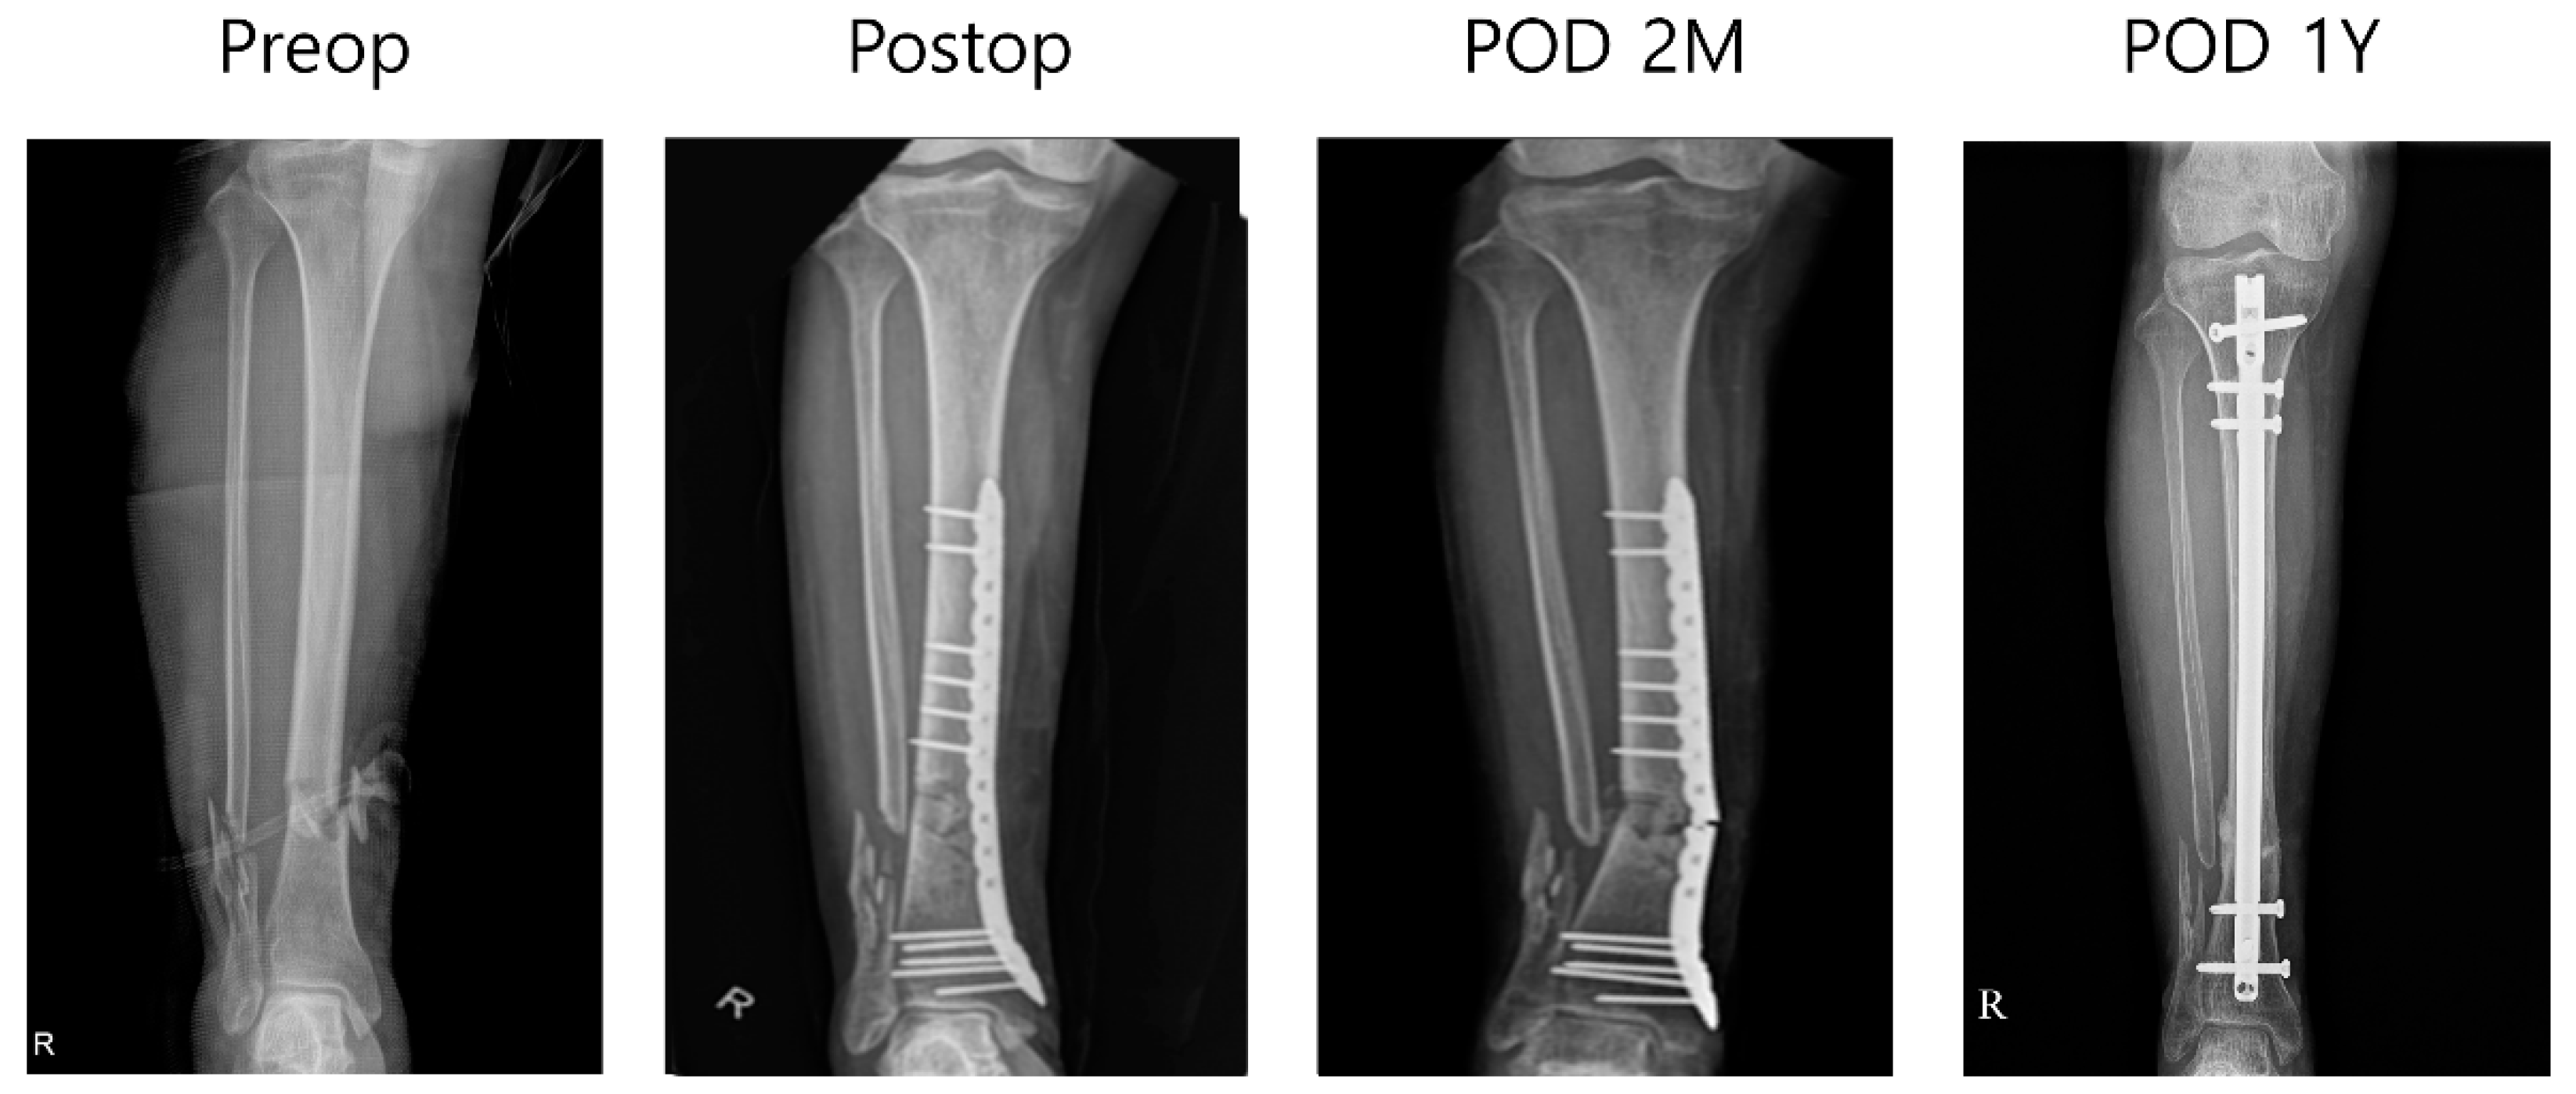

Ten tibial fractures that underwent surgical reduction were followed up for 1–2 years. Over the follow-up period, in nine out of 10 tibiae, the fracture plate remained undamaged, deformed, and securely fixed within the body. The mean American Orthopedic Foot and Ankle Society (AOFAS) score was 81.3 (SD 5.7). In one patient, who experienced failed fracture healing and had neurofibromatosis type 1, the fracture plate did not fulfill its intended role in the case of an open fracture. Consequently, revision surgery was performed using a tibial intramedullary nail and additional bone grafting. A biopsy of the previously failed fracture site revealed chronic inflammation with fibrosis and dead bone particles (Figure 4).

Figure 4.

Failed fracture plate case: A 59-year-old female pedestrian was diagnosed with an open tibiofibular shaft fracture and subdural hematoma (SDH) following a traffic accident in which she was hit by a taxi. The patient had a medical history of neurofibromatosis. After massive irrigation and confirmed wound stabilization, minimally invasive percutaneous plating (MIPO) using a 3D-printed plate was performed 4 days after the trauma. The wound healed well without an additional coverage operation. Partial weight bearing was initiated 6 weeks post-operation. Three months post-operation, the patient presented to the outpatient clinic with lower leg pain; a plain radiograph confirmed plate breakage. She subsequently underwent reoperation with plate removal and conversion to an intramedullary (IM) nail fixation. An intraoperative biopsy of the nonunion site revealed findings consistent with chronic inflammation with fibrosis and the presence of dead bone fragments. After tibia IM nail fixation, fracture union was achieved, and the patient’s AOFAS score was 70. R means right sided.